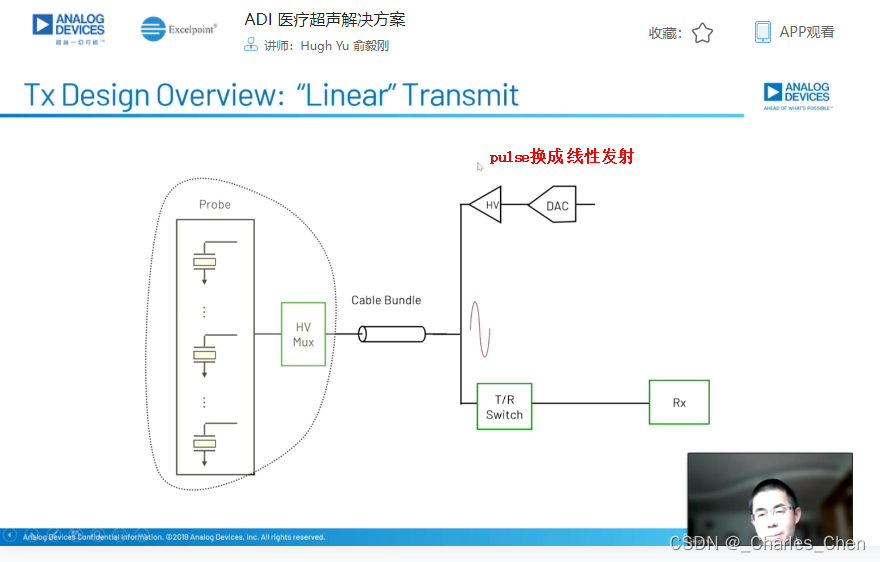

数字发射波束成形器用于产生所要求的数字发射信号,以正确的时间和相位生成聚焦发射信号。高性能超声系统可通过任意波形发生器产生复杂的发射波形,从而优化图像质量。这些情况下,发射波束成形器以大约40MHz速率生成8位至10位数字字符,并以此产生所要求的发射波形。数/模转换器(DAC)将数字波形转换成模拟信号,通过线性高压放大器进行放大,用于驱动传感器单元。由于这种发射技术占用较大体积,而且价格昂贵、需要消耗较高能量,所以,这种架构只限于昂贵的非便携设备。多数超声系统并不使用这种发射波束成形技术,而是采用多级高压脉冲发生器产生需要发射的信号。在这种替代方案中,利用高集成度、高压脉冲发生器快速切换传感器单元至适当的可编程高压电源,产生发射波形。为了产生一个简单的两极发射波形,脉冲发生器需要交替地将传感器单元切换到由数字波束成形器控制的正、负发射电压。更复杂的设计可以让传感器单元切换至多路电源和地,从而产生更复杂、性能更好的多重波形。